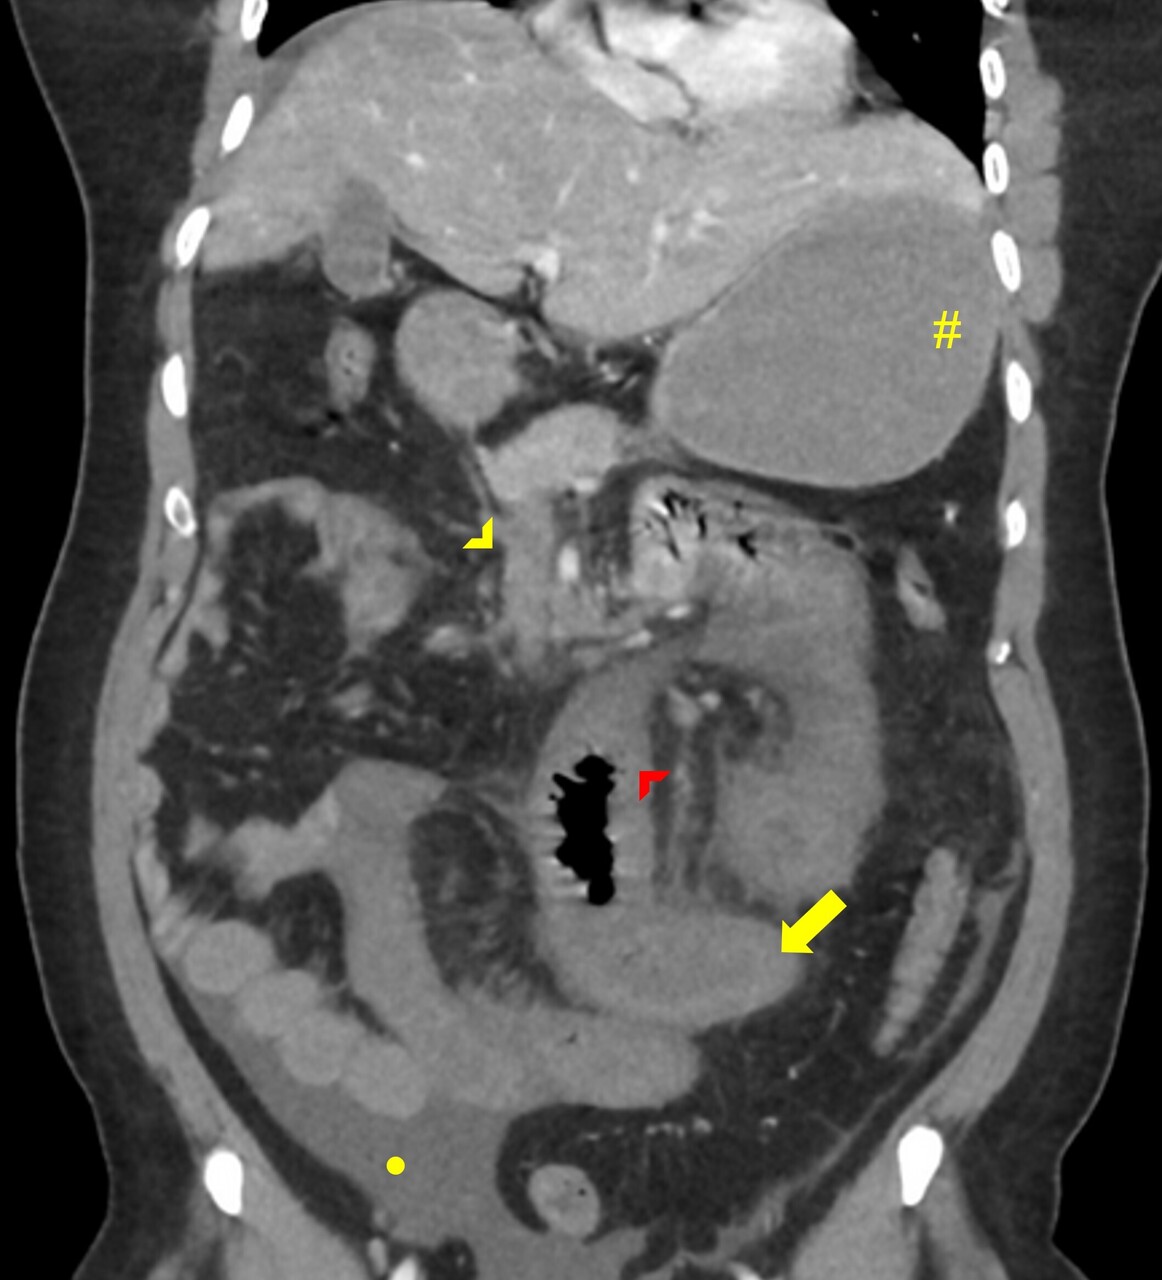

Le diagnostic de TVP récente repose sur l’imagerie. Elle doit être réalisée chez tout patient qui en présente une suspicion clinique. L’échographie-Doppler est généralement l’examen de première intention  ; elle permet la visualisation directe du thrombus dans la veine porte et l’absence de flux au Doppler en cas de TVP complète (sensibilité de 88 à 98  %, spécificité de 80 à 100  %). Elle doit être complétée systématiquement par un scanner (ou une imagerie par résonance magnétique [IRM]) abdominal avec injection de produit de contraste, et aux quatre temps d’acquisition (sans injection, phase artérielle, portale et tardive), si cette imagerie n’a pas été réalisée d’emblée. Le scanner permet de confirmer le diagnostic de TVP, de déterminer le degré d’extension aux veines spléniques et mésentériques, de rechercher un facteur local et des signes d’ischémie mésentérique. De plus, il permet d’identifier des signes d’hépatopathie chronique sous-jacente (dysmorphie hépatique, signes d’hypertension portale) [fig. 2].

Une ischémie mésentérique est recherchée systématiquement sur le scanner abdominal aux quatre temps (sans injection, temps artériel, portal et tardif) et est confirmée par la constatation de signes de souffrance intestinale associés à la TVP tels qu’un épaississement de la paroi intestinale et/ou une diminution de rehaussement des anses après injection de produit de de contraste. La mise en évidence d’une absence de rehaussement pariétal, d’une dilatation intestinale supérieure à 25 mm ou encore d’une pneumatose intestinale voire aéroportie (présence de gaz dans la lumière de la veine porte) sont des signes de gravité évoquant une nécrose intestinale et indiquant un traitement chirurgical.